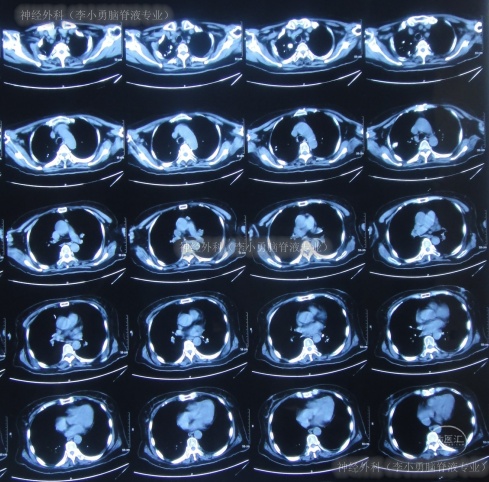

脑室腹腔分流术后2天即2012年12月6日,查头颅CT示无异常(图-20),查肺部CT示感染进一步减轻(图-21)。

图-21:2012年12月6日肺部CT